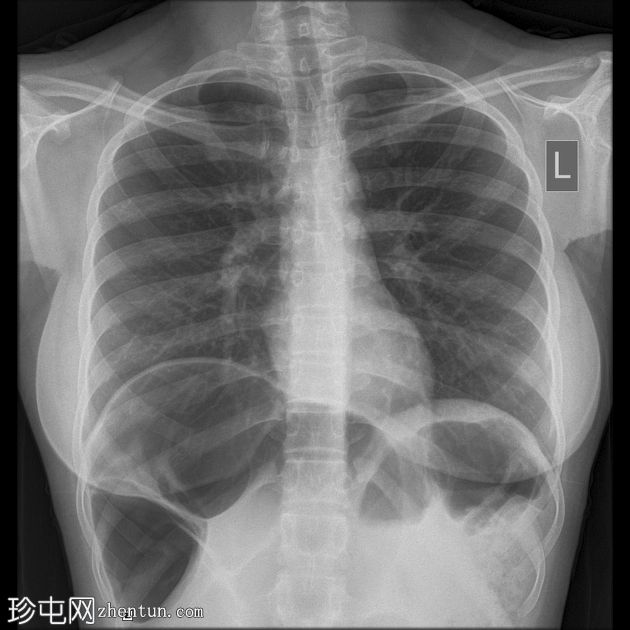

X光片

右侧膈肌抬高,原因是结肠位于肝脏和抬高的膈肌之间。

Chilaiditi征是一种罕见且常为偶然发现的胸腹部常规X光片征象,据报道其发生率在0.025%至0.28%之间<sup>3</sup>。其特征是肠道(通常是结肠)位于肝脏和膈肌之间。易感因素包括悬韧带松弛、先天性肠管错位和突发性体重下降。

Chilaiditi征可能被误诊为气腹,而气腹在急性腹痛的情况下被视为急症。因此,Chilaiditi征是假性气腹的病因之一。

当 Chilaiditi 征伴有腹痛、呼吸困难、便秘、恶心和/或呕吐等症状时,就称为 Chilaiditi 综合征。